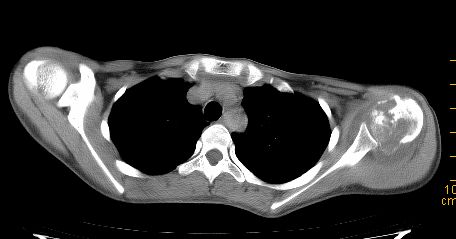

标题: CT22395:左侧肱骨头占位性病灶。 [打印本页]

标题: CT22395:左侧肱骨头占位性病灶。

这是一个17岁的花季少女,在上学期间,自觉左侧肩部不适,家人误以为是外伤引起,没有重视,近日疼痛加剧,来院就诊,ct检查发现如下.

诊断依据:1、骨质破坏,软组织肿胀。2、从纵隔窗上看,这么年轻就有纵隔淋巴结钙化,提示有可能有肺结核病史,这是诊断左肩关节结核的又一重大证据,建议结合病史并提供肺窗。

鉴别诊断:成软骨细胞瘤(位于骨骺内,囊状破坏,一般不会有软组织肿胀)

骨质膨胀性破坏,软组织肿胀,有新骨形成。考虑骨肉瘤